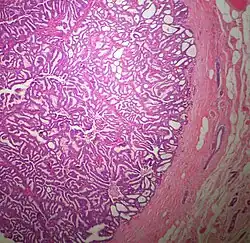

The microscopic histopathology of typical PDCIS lesions (refer to adjacent high-power photomicrograph) prepared with a hematoxylin and eosin stain consists of mammary ducts that have papillary fronds (i.e. thin, finger-like or leaf-like structures) lined with one or several layers of neoplastic, columnar-shaped epithelial cells (i.e. tall, narrow cells with their nuclei close to the site of their ductal attachment).[4] The fronds have branching fibrovascular cores. Epithelial cells lining the fronds' inner surfaces commonly form solid, cribriform (i.e. large nests of cells perforated by many rounded, variably sized spaces), or micro-papillary patterns. There may be a second population of epithelial cells lining the papillae that have abundant clear cytoplasm in addition to the usual neoplastic epithelial cells which line the papillae. These cells, which are not myoepithelial cells, have been termed globoid cells.[7] They have eosinophilic cytoplasm (i.e. pink or red cytoplasm due to its uptake of eosin stain).[6] PDCIS tumors with these cells have been termed dimorphic variants of PDCIS.[3] Myoepithelial cells are typically present at the periphery of the fronds but absent within the involved ducts.[4][7] The presence of a fibrous capsule and/or absence of peripherally located myoepithelial cells are strong indicators that the tumor is an ESP rather than a PDCIS.[3] PDCIS tissues may also contain areas of "Comedo-type necrosis", i.e. areas where dead cells have accumulated.[6]